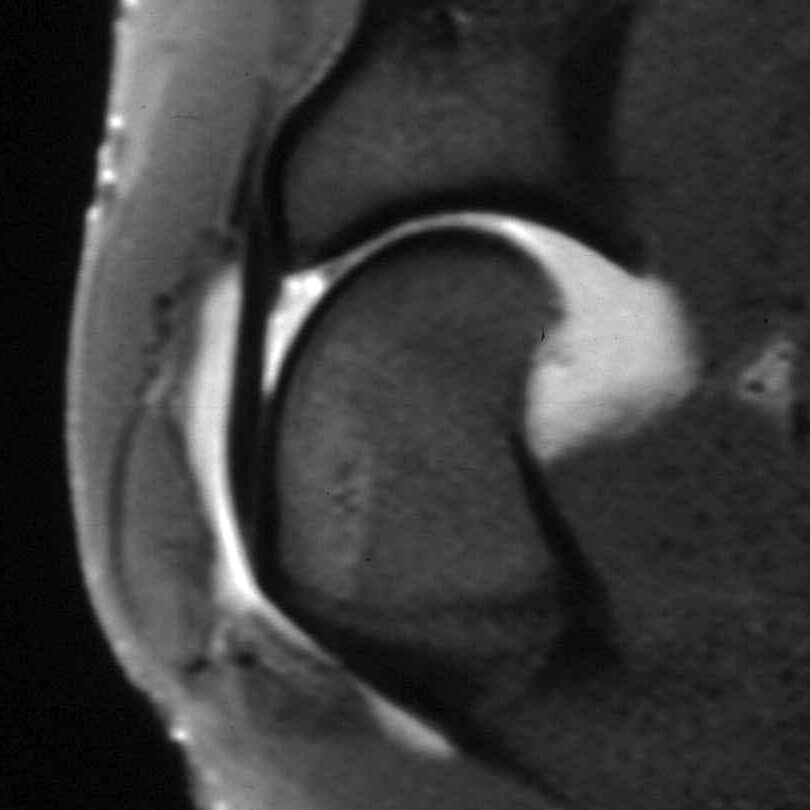

Osteochondritis dissecans is a developmental disorder of larger breed dogs that typically starts to cause signs at 5-7 months of age, but sometimes later. Breeds affected by OCD include giant breeds such as Great Danes and popular breeds such as Labrador and Golden Retrievers, as well as Border Collies. The cause is not clear but it is more common in male dogs. It represents a failure of the joint surface to develop correctly and the cartilage, which lines the joint surface, can become partially detached from the underlying bone; this causes pain and because the cartilage is typically partially detached, the underlying tissue cannot heal.

Recommended treatment for OCD that is causing persistent pain is surgical removal of the loose cartilage and, in our opinion, this is best performed with keyhole surgery (arthroscopy). Arthroscopy minimises trauma to the soft tissues and allows for a rapid recovery. In addition, arthroscopy provides the surgeon with magnification and access to all parts of the joint.